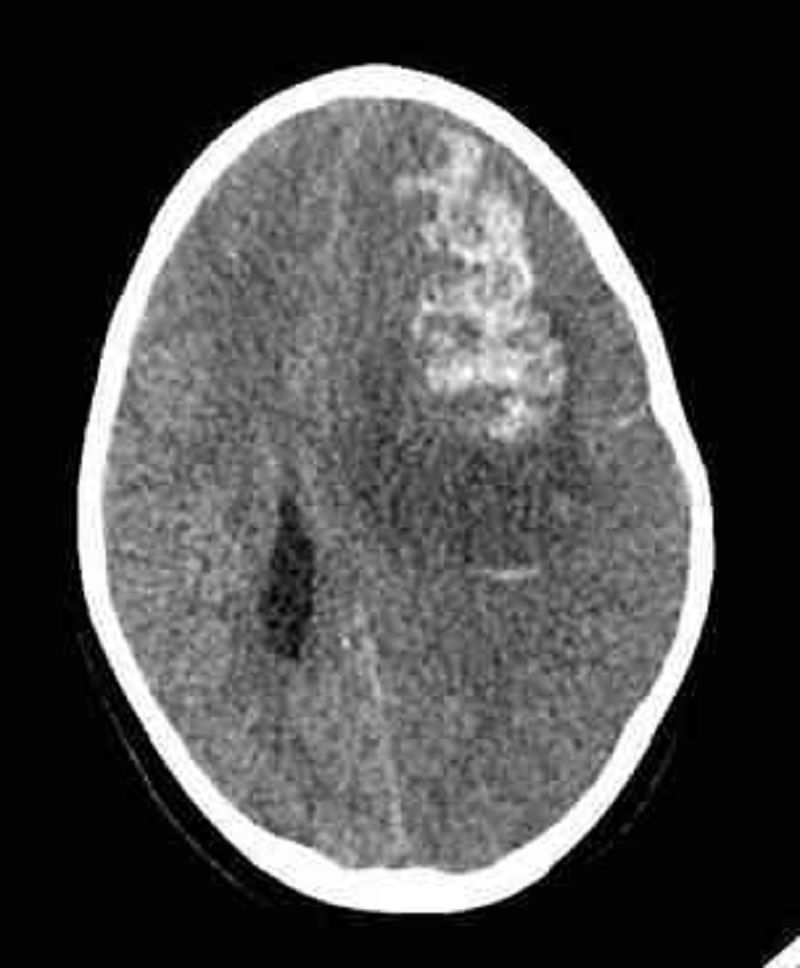

Vous faites réaliser un scanner cérébral non injecté, ci-joint, à un enfant de 6 ans suivi pour une aplasie médullaire idiopathique profonde évoluant depuis 3 mois (GB < 0,5 G/L, plaquettes < 20 G/L) et qui vient tout juste d'être admis en réanimation pédiatrique pour état de mal épileptique. Quel est le diagnostic le plus probable ?

Une hémorragie intracérébrale

Un accident vasculaire cérébral

Une tumeur intracranienne

Un abcès intracranien

Une méningoencéphalite